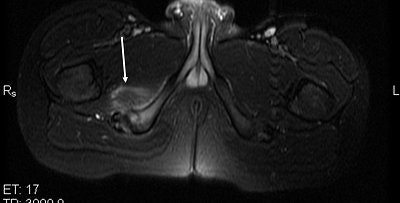

Plain radiographs, including an anteroposterior view of the pelvis, showed an avulsion of the right ischial tuberosity in the typical inferolateral location. An MR exam demonstrated osseous and soft-tissue edema, along with an avulsion fracture of the right ischial tuberosity (Figures 1-4).

| Figure 2. Axial T2-weighted MR image of the pelvis shows increased signal within the soft tissue adjacent to the right ischial tuberosity (white arrows). |